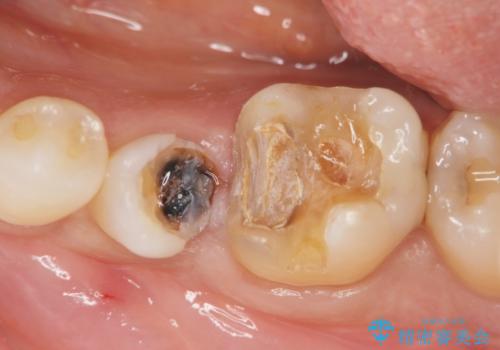

- 「歯がぐらぐらして噛めない、歯を抜いて欲しい、またしっかりと噛めるようになりたい。」、と歯周病治療を希望され来院されました。

歯の根本まで骨吸収が進み、ぐらぐらになってしまった歯を抜去し骨の造成を行ったのちインプラント治療を計画します。